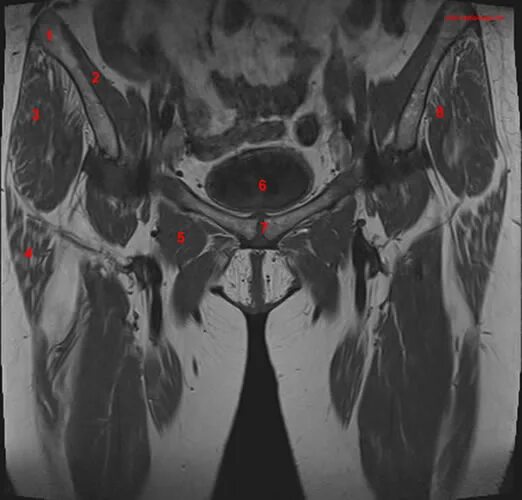

Мрт тазобедренного сустава в минске